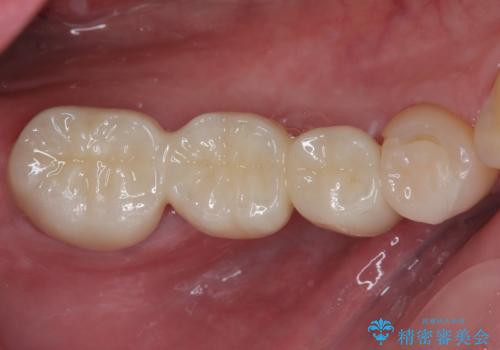

詰め物が割れた フルジルコニアクラウン

- 左下の4番目のセラミックの詰め物(セラミックインレー)が欠けたとのことで来院された患者様です。以前にセラミックの詰め物の治療を行い、噛み合わせが強く割れてしまっていました。今回はセラミックの詰め物のやり替えだとまた欠けてしまう可能性があるのでフルジルコニアクラウンでの治療を行うことにしました。拡大鏡視野下でセラミックの詰め物、虫歯を除去しフルジルコニアクラウンに適した形に整えました。

歯と歯茎の間に圧排糸と呼ばれる糸を入れてシリコーン印象を行いました。

見た目、機能面ともに満足していただけました。

噛み合わせが強い方なので今後はセラミックが割れないようにナイトガードを使っていただきながら、定期的にクリーニングで通ってもらう予定です。